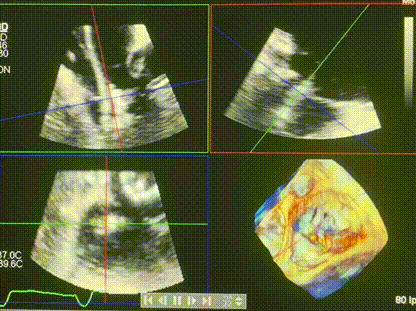

術(shù)后超聲顯示僅殘余微量瓣周漏

LuX-Valve Plus經(jīng)血管三尖瓣置換系統(tǒng)此次“出海”圓滿完成,術(shù)后Rodrigo Estévez-Loureiro教授對LuX-Valve Plus經(jīng)血管三尖瓣置換系統(tǒng)的器械性能和治療效果大為稱贊,認(rèn)為LuX-Valve Plus的手術(shù)體驗非常好。術(shù)后即刻超聲顯示三尖瓣反流幾乎完全消失,血流動力學(xué)改善顯著,患者恢復(fù)快。在面對復(fù)雜解剖結(jié)構(gòu)、超聲影像質(zhì)量不佳、有起搏導(dǎo)線干擾時,Lux-Valve Plus也體現(xiàn)了極強的適應(yīng)性。Thomas Modine教授和Anson Cheung教授也肯定了LuX-Valve Plus術(shù)中操作的便捷性,認(rèn)為LuX-Valve Plus容錯率高,對術(shù)中影像的依賴較小,后期希望可以更多的應(yīng)用LuX-Valve Plus三尖瓣置換系統(tǒng)于臨床實踐,讓更多的三尖瓣重度反流患者盡早獲益,改善預(yù)后。